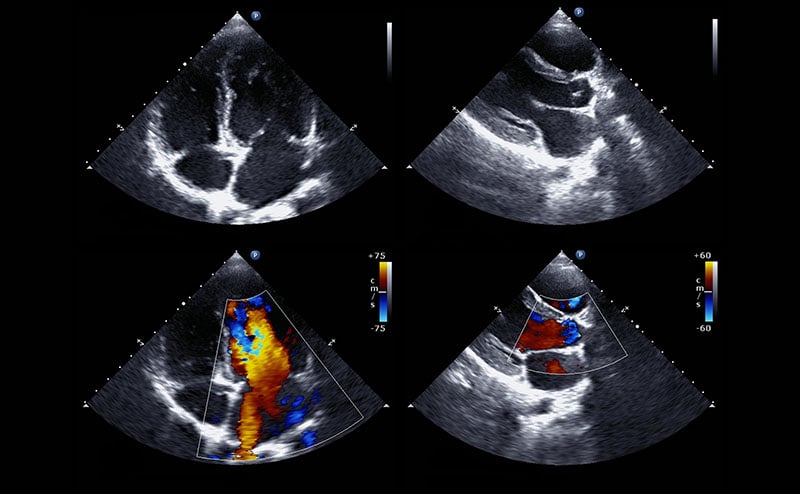

The “pump” or the heart is the first step in evaluating the undifferentiated pediatric patient in shock and their response to treatments rendered. It is evaluated in the four traditional cardiac views - parasternal long and short, subxiphoid, and apical 4 chamber. These views evaluate for pericardial effusion (including tamponade physiology), contractility, chamber dilation and sufficient filling. Decreased left ventricular (LV) contractility can indicate cardiogenic failure. Decreased LV filling can indicate problems with venous return such as obstruction of right heart blood flow or hypovolemia. Right ventricular (RV) strain or dilation may indicate pulmonary embolism. A decrease in RV filling suggests blood loss or potential neurogenic or infectious causes requiring pharmacological intervention with vasopressors or inotropes. A pericardial effusion can be assessed for tamponade physiology, and ultrasound guidance can be used to perform pericardiocentesis as indicated. Global heart dilation and or poor “squeeze” can be seen in myocarditis.

This clip displays cardiac tamponade with a large pericardial effusion. The effusion is causing diastolic collapse of the right ventricle and is concerning for tamponade physiology.

This video displays severe LV dilatation and systolic dysfunction with moderate inferior pericardial effusion. The patient ultimately was diagnosed with Anomalous Left Coronary Artery from the Pulmonary Artery (ALCAPA). In this process, the left coronary artery (LCA) arises from the pulmonary artery instead of the aorta, leading to a reversed blood flow and reduced oxygen supply to the heart muscle, causing ischemia and potentially heart failure.